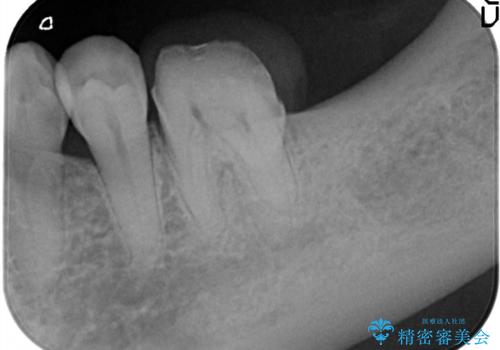

- 左下の1番後方の歯が欠損しており、インプラントにて咬合回復する計画としました。

レントゲン・CT撮影により骨の高さがあまりないことがわかり、ショートインプラントを選択しました。